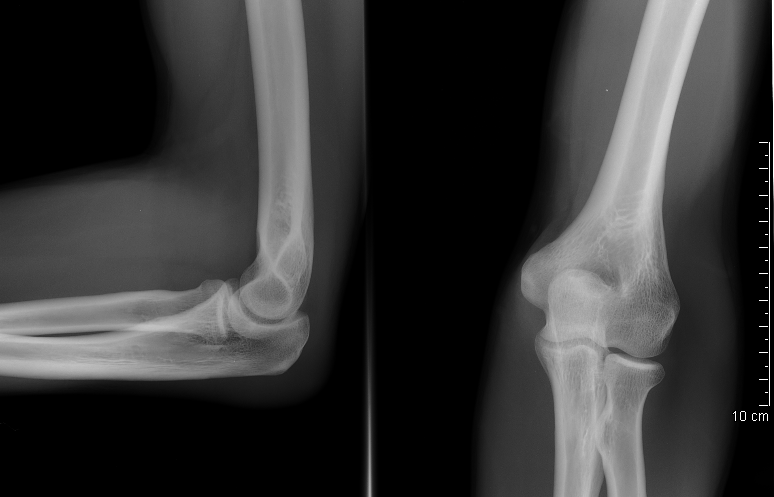

4. 1. 단순 X선 촬영

단순 X선 촬영은 물체를 X선 또는 기타 고에너지 형태의 전자기파에 노출시켜 생성된 잔류 빔(또는 "음영")을 잠상으로 포착하여 이미지를 생성하는 "투사 방사선 촬영"의 일종이다.[32] 뼈와 일부 장기(예: 폐)는 투사 방사선 촬영에 적합하며, 비교적 저렴한 검사로 높은 진단 수율을 보인다.[32] 뢴트겐이 X선을 발견한 이후, 의료 분야에서는 주로 뼈나 폐의 병변을 그려내는 영상 진단으로서 적극적으로 이용되어 왔다.

단순 X선 촬영의 주요 이용법은 다음과 같다.